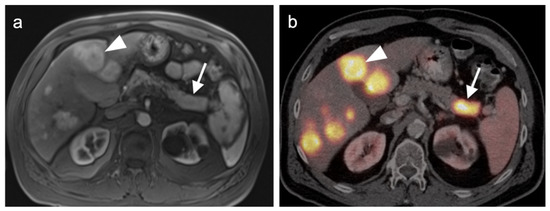

- Gao, Y.-J.; Yang, Z.; Yu, J.-Y.; Li, N.; Wang, X.-J.; Zhou, N.-N. Potential application value of PET/computed tomography in retroperitoneal leiomyosarcoma and a literature review. Nucl. Med. Commun. 2021, 42, 800–810. [Google Scholar] [CrossRef]

- Subramaniam, S.; Callahan, J.; Bressel, M.; Hofman, M.S.; Mitchell, C.; Hendry, S.; Vissers, F.L.; Van der Hiel, B.; Patel, D.; Van Houdt, W.J.; et al. The role of 18 F-FDG PET/CT in retroperitoneal sarcomas—A multicenter retrospective study. J. Surg. Oncol. 2021, 123, 1081–1087. [Google Scholar] [CrossRef]